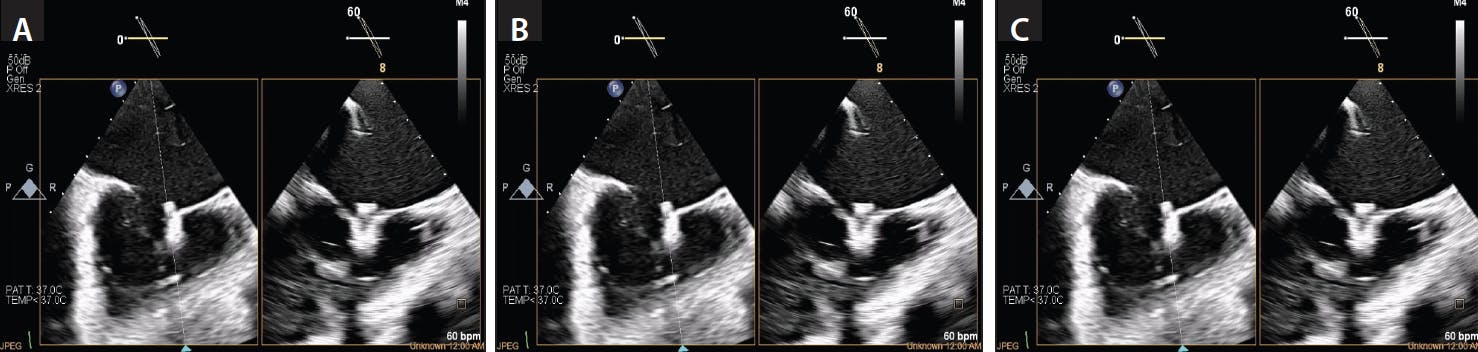

Figure 6. MPR view identifying the TV leaflets in 3D views. Once the RV inflow view (upper left panel) is acquired, multiplane feature simultaneously identifies the orthogonal view (upper right panel), with an en-face reconstructed 2D view (bottom left panel) and 3D en-face atrial view (bottom right panel) with the AcuNav catheter (A) and using the VeriSight Pro (B) in real time. The green circular cursor can be placed to identify the septal, anterior, and posterior leaflet on multiple views. AV, aortic valve.

The initial 3D ICE imaging for the TV is the home view position in the right atrium (RA) with and without color to identify all three TV leaflets and origination of the TR jet (Figure 4). Biplane images are obtained to determine the area of maximum regurgitation and full anatomic assessment, including an RV inflow/outflow view (Figure 5). A multiplane reconstruction (MPR) view is obtained by placing the crosshair markers across the TV, creating a 3D en-face view of the TV in real time. Ideally, the aortic valve is placed at the nine o’clock position to help identify all leaflets in a consistent manner, according to this anterior landmark. From this view, anterior, posterior, and septal leaflets are identified (Figure 6). The TV often has more than three leaflets. The steerable guide catheter (SGC) is identified in the RA, and the clip delivery system (CDS; Abbott) is viewed while exiting the SGC. The CDS is steered from the septal side of the RA toward the TV, and the clip is positioned above of the TV regurgitant jet.

Orthogonal views with biplane or real-time 3D MPR can be displayed simultaneously (Figure 7). The tricuspid clip is opened above the TV, aligned above the TV, and advanced into the RV just below the targeted leaflets with the orthogonal views as guidance. If the desired grasping area is located along the anteroseptal commissure, the grasping view will typically show the anterior and septal leaflets on top of the tricuspid clip arms (Figure 8). The absence of acoustic interference of the CDS at the level of the tricuspid leaflets is a distinct imaging advantage with 3D ICE. This facilitates proper leaflet grasping with no need for catheter manipulation, allowing the operator to maintain the delivery system in plane throughout grasping. Crosshair alignment of the image is used to properly orient the clip with TV leaflets, confirming of insertion of both anterior and septal leaflets. Doppler flow is used to determine residual regurgitation and need for additional clip placement.